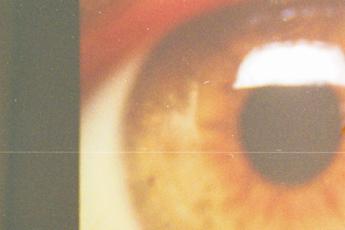

(Adnkronos) – Era dicembre 2023 quando veniva annunciato che Holostem, l'azienda biotech di Modena nata per sviluppare terapie avanzate a base di cellule staminali e impegnata da anni per dare una speranza di terapia ai 'bambini farfalla', affetti da una rara malattia genetica, l'epidermolisi bollosa, era ufficialmente salva. Scongiurata la liquidazione, infatti, con l'intervento del ministero del Made in Italy e delle Imprese (Mimit) era stato avviato il percorso di acquisizione da parte della Fondazione Enea Tech e Biomedical. Il 2024 è stato l'anno del rilancio a livello internazionale sul fronte dello sviluppo di terapie cellulari e geniche per malattie rare e senza rimedio. Un rilancio che passa anche da una terapia salva-cornea. Il 7 gennaio 2025, al Centre Hospitalier Universitaire de Liège, il professore Bernard Duchesne ha effettuato con successo la biopsia alla cornea di un giovane paziente che aveva subito un'ustione causata da agente chimico durante un'aggressione. Il giorno successivo alla biopsia, il team di esperti dell'officina farmaceutica Gmp della Holostem, nel Centro di medicina rigenerativa dell'università di Modena e Reggio Emilia, è stato in grado di estrarre le cellule staminali limbari della cornea per la preparazione della terapia Holoclar. Una accurata conta, estrazione e crescita delle staminali limbari è la condizione essenziale per lo sviluppo della terapia cellulare destinata all'impianto sul paziente, che è possibile ad oggi mettere in atto soltanto nei laboratori di Holostem. Altri pazienti sono già in lista per l'avvio della terapia a febbraio. La terapia Holoclar è stato il primo prodotto di terapia cellulare al mondo che ha avuto nel 2015 il Conditional Approval per l'immissione in commercio in Ue e nel Regno Unito, rispettivamente dagli enti regolatori Ema (Agenzia europea del farmaco) e dalla britannica Mhra (Medicines and Healthcare products Regulatory Agency), ottenendo poi la Full Marketing Authorization nel primo semestre del 2024. Merito del risultato, ha sottolineato l'Ad della società, Alessandro Padova, deve essere riconosciuto al team di Holostem che ha lavorato incessantemente, con passione e impegno, per mettere di nuovo a regime i laboratori altamente specializzati dell'officina Gmp e far ripartire la produzione del prodotto cellulare terapeutico. La commercializzazione di Holoclar, spiegano da Holostem in una nota, rappresenta l'avvio del nuovo piano industriale di Holostem che inoltre "prevede la creazione di attività ed investimenti finalizzati alla scoperta e sviluppo di terapie innovative personalizzate per malattie rare ad oggi senza terapia risolutiva, con un approccio di open innovation attraverso importanti partnership strategiche con centri ospedalieri italiani ed europei". Il valore dell'innovazione e competitività dell'azienda, prosegue la nota, è stato riconosciuto anche dalla Commissione europea che ha selezionato Holostem per avere accesso ai finanziamenti Ipcei (Importanti Progetti di Comune Interesse Europeo) Med4Cure, in quanto una tra le 13 aziende europee in grado di perseguire l'obiettivo di sostenere la realizzazione di progetti innovativi e di rilevanza strategica per salute e sanità, al fine anche di migliorare la qualità e l'accesso alle cure del paziente. "Senza l'apporto di ciascuno dei componenti del Consiglio di amministrazione ed il contributo del Collegio dei sindaci non sarebbe stato possibile, in un contesto estremamente complesso, arrivare alla definizione del piano industriale della società e così permettere all'azienda di ripartire nelle attività di produzione e ricerca – commenta il presidente della Holostem, Francesco Vetrò, manifestando soddisfazione per il risultato raggiunto – Il risultato, tuttavia, non sarebbe stato neppure lontanamente alla portata se la Fondazione Enea Tech e Biomedical ed il Mimit non avessero con lungimiranza salvaguardato e rilanciato un'azienda unica nel settore in Italia e all'estero". E, ricorda ancora, "nulla si sarebbe potuto realizzare se non vi fosse stato l'iniziale apporto di risorse della Chiesi Farmaceutici e senza la partnership con l'università di Modena e Reggio Emilia". —salutewebinfo@adnkronos.com (Web Info)